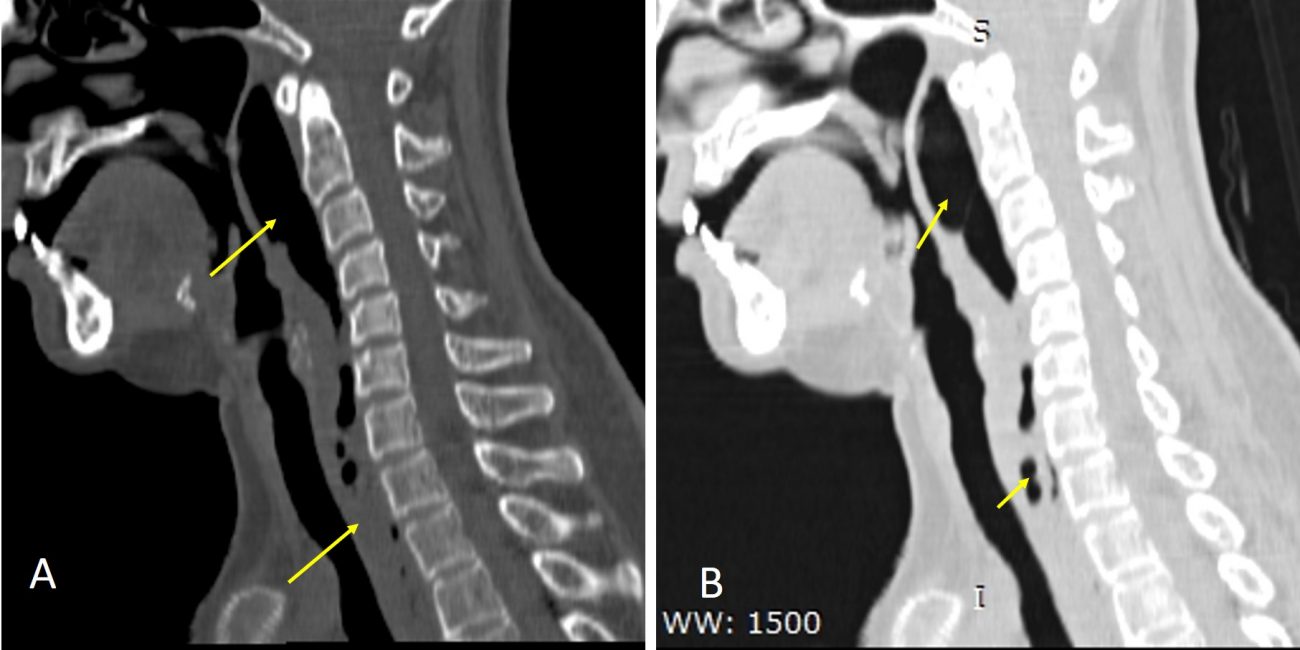

Pyogenic spondylodiscitis with paraspinal abscess Radiology Cases Abscess X Ray View Lung abscess is a type of liquefactive necrosis of the lung tissue and formation of cavities (more than 2 cm) containing necrotic debris or fluid. This patient has a lung cavity. Typical radiological appearances are of a central zone of necrotic inflammatory material encapsulated by a discernible wall. Notice the acute angle the abscess makes with the posterior chest wall.. Abscess X Ray View.